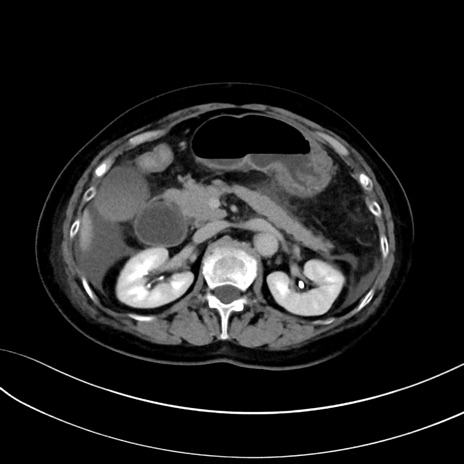

症例13 CT(横断像)1日半後

(冠状断像)1日半後